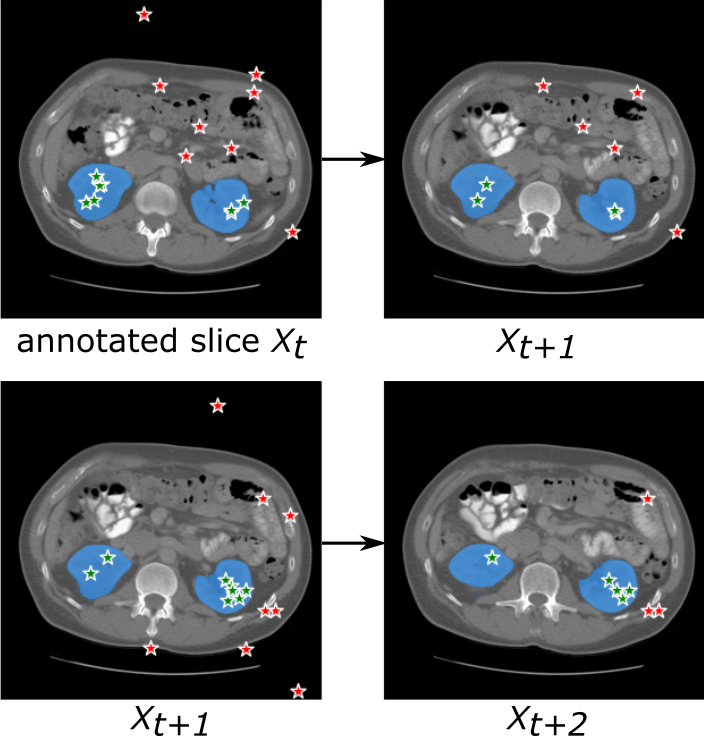

3.2.2

In contrast to the SAM model, the SAM model is designed to automatically generate the annotations without user interaction. SAM aims to further boost medical annotation procedures. The architectural framework of SAM is illustrated at Fig. 3. Instead of relying on manual input prompts from users, we introduce a “prompt generator” module, denoted as , which automatically generates potential prompts for the query images. This module is trained on a limited number of manually annotated slices. The image segmentation module employed in the SAM is the pre-trained SAM model. Therefore the objective of SAM module can be described as follows:

Consequently, the primary challenge lies in developing an app)ropriate prompt generator for the SAM model. There are various approaches can be explored for generating the prompts for query image slices. In this study, we mainly investigated three approaches:

Prompt propagation

Taking inspiration from numerous label propagation approaches, prompt propagation is a straightforward and intuitive approach to generate potential prompts for new images. Considering the consistency between medical image slices, prompt propagation can effectively deduce the possible prompts based on annotated seed prompts. Nevertheless, one of the key challenges in employing the prompt propagation approach is how to establish an appropriate propagation criterion. Additionally, several inherent drawbacks of prompt propagation remain to be addressed. Firstly, it cannot handle discrete objects, such as nuclei and lung nodule segmentation tasks. Secondly, propagating the background prompts is difficult due to its diverse tissues composition.

In this work, we implemented a simple prompt propagation strategy by dynamic thresholding approach. The specific algorithmic details can be found in Algorithm 1. The foreground points will be recursively propagate to the neighboring slices based on intensity consistency principles.

As for the ‘prompt propagation’ strategy described in Algorithm 1, the points that are randomly selected from the annotated slices will undergo propagation to the neighboring slices utilizing a straightforward thresholding rule. This iterative procedure will terminate when there are no points satisfying the specified criterion. To improve the robustness, the propagation is individually applied to each annotated slice. Consequently, in the case of two annotated slices, the propagation is executed twice, and the resulting segmentation are then ensemble to obtain the final segmentation. One example of point propagation procedure is shown in Figure 11.